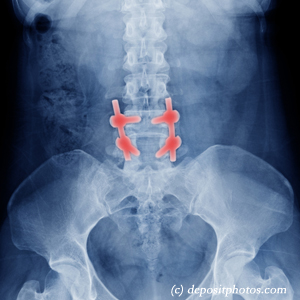

Back pain that persists after back surgery can feel like a distressing setback, leaving many patients like you or your loved one discouraged when conventional treatments fall short. Cox® Technic, a specialized form of chiropractic distraction spinal manipulation, offers a promising conservative treatment option. This gentle technique utilizes a specially designed table for controlled distraction treatment of the low back, creating decompression while mobilizing restricted segments.

Cox® Technic works by gently decompressing spinal discs, boosting nutrient flow, and restoring healthy spine movement—all without the need for more forceful adjustments. This makes it especially suitable for post-surgical patients needing gentle, precise treatment that respects altered spinal anatomy while addressing ongoing pain and dysfunction.